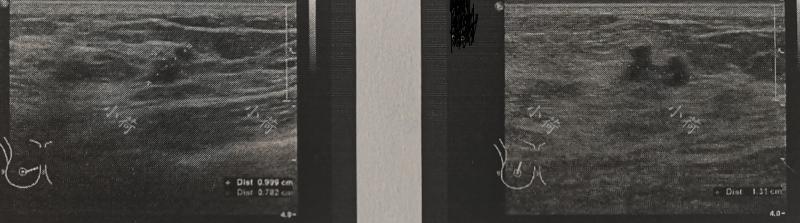

2年前,门诊一位40多岁的中年女性患者来门诊就诊,患者描述3天出现右侧乳头血性溢液,自行按摩后,未再出现乳头溢液情况,患者行彩超检查及钼靶检查,B超显示右乳多发低回声结节(图1)。询问病史患者已经有5年未行体检,而且根据患者的检查结果不排除恶性肿瘤可能,收住院限期行手术治疗。

图1 B超显示右乳多发低回声结节